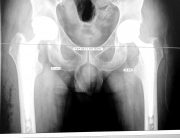

Técnica Quirúrgica: Abordaje Anterior

Otra pieza importante para conseguir nuestro objetivo de no transfusión, es

la técnica quirúrgica. En mi caso, desde hace unos años opero las prótesis de

cadera mediante el Abordaje Anterior.

Con este abordaje entraremos a la articulación por la parte delantera de la cadera, es un abordaje poco invasivo . No cortamos tendón ni ningún o músculo, logrando con esto además de disminuir el riesgo de luxación y mejorando la recuperación y disminuyendo el dolor.